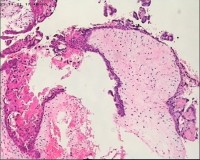

性别

女

年龄

20岁

临床诊断

一般病史

停经3月,阴道不规则流血7天。

标本名称

宫刮物

大体所见

灰白灰红碎组织一堆,大小为7*6*1cm,部分组织呈水泡状

水肿的绒毛和蜕膜,没看到增生的滋养细胞。必要时可做IHC除外部分葡萄胎,并结合临床HCG。

考虑葡萄胎